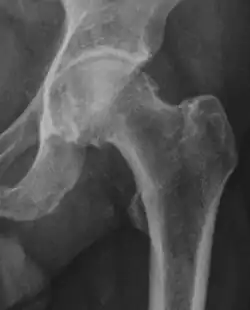

Three types of FAI are recognized (see title image). The first involves an excess of bone along the upper surface of the femoral head, known as a cam deformity (abbreviation for camshaft, which the shape of the femoral head and neck resembles). The second is due to an excess of growth of the upper lip of the acetabular cup and is known as a 'pincer' deformity. The third is a combination of the two, generally referred to as 'mixed.' The most common type seen, approximately 70% of the time, is the mixed type.[13] A complicating issue is that some of the radiographic findings of FAI have also been described in asymptomatic subjects.[14]

Current literature suggests that the cam type of impingement is associated with the development of hip osteoarthritis.[15] Thus far, no correlation has been seen between the pincer type and development of hip osteoarthritis.[15]